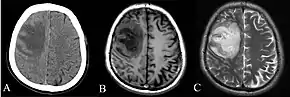

Chest X-ray showing opacity of the left middle and lower areas of the lung.[6]

CT and MRI scans showing lesion of the right frontal lobe of the brain.[6]

Diabetes mellitus is one of the most important risk factors in developing melioidosis. The disease should be considered in anyone who has spent time in endemic areas who develops a fever, pneumonia, or abscesses in their liver, spleen, prostate, or parotid gland.[1] The clinical manifestation of the disease can range from simple skin changes such as abscesses or ulcerations to severe organ problems.[8] The commonest organs affected are liver, spleen, lungs, prostate, and kidneys. Among the most common features are bacteremia (in 40 to 60% of cases), pneumonia (50%), and septic shock (20%).[1][9] People with only pneumonia may have a prominent cough with sputum and shortness of breath. However, those with septic shock together with pneumonia may have minimal coughing.[2] Results of a chest X-ray can range from diffuse nodular infiltrates in those with septic shock to progressive consolidation located most commonly in the upper lobes for those with pneumonia only. Pleural effusion and empyema are more common for melioidosis affecting lower lobes of the lungs.[2] In 10% of cases, people develop secondary pneumonia caused by other bacteria after the primary infection.[3] In northern Australia, 60% of the infected children presented with only skin lesions, while 20% presented with pneumonia.[3]

Depending on the course of infection, other severe manifestations develop. Approximately 1 to 5% of those infected develop inflammation of the brain and brain covering or brain abscess; 14 to 28% develop pyelonephritis, kidney abscess or prostatic abscesses; 0 to 30% develop neck or salivary gland abscesses; 10 to 33% develop liver, spleen, or paraintestinal abscesses; and 4 to 14% develop septic arthritis and osteomyelitis.[1] Rare manifestations include lymph node disease resembling tuberculosis,[10] mediastinal masses, pericardial effusion,[3] mycotic aneurysm,[1] and inflammation of the pancreas.[3] In Australia, up to 20% of infected males develop prostatic abscess which may manifests clinically as pain during urination, difficulty in passing urine, and urinary retention requiring catheterisation.[1] Rectal examination may find enlarged prostate.[3] In Thailand, 30% of the infected children develop parotid abscesses.[1] Encephalomyelitis not only happens in those with risk factors, but can also occur in healthy people without risk factors. Those with melioidosis encephomyelitis tend to have normal computed tomography (CT) scans but increased T2 signal by magnetic resonance imaging (MRI), extending to the brain stem and spinal cord. Clinical signs include: unilateral upper motor neuron limb weakness, cerebellar signs, and cranial nerve palsies (VI, VII nerve palsies and bulbar palsy). Some cases presented with flaccid paralysis alone.[3] In northern Australia, all melioidosis with encephalomyelitis cases had elevated white cells in the cerebrospinal fluid (CSF), mostly mononuclear cells with elevated CSF protein.[10]

Various imaging modalities can also help with the diagnosis of melioidosis. In acute melioidosis with the spreading of the bacteria through the bloodstream, the chest X-ray shows multifocal nodular lesions. It may also show merging nodules or cavitations. For those with acute melioidosis without the spread to the bloodstream, chest x-ray most commonly shows upper lobe consolidation or cavitations.[10] In chronic melioidosis, the slowly progressing of upper lobe consolidation of the lungs resembles tuberculosis.[10] For abscesses located in other parts of the body apart from the lungs, especially in the liver and spleen, CT scan has higher sensitivity when compared with an ultrasound scan. In liver and splenic abscesses, an ultrasound scan shows "target-like" lesions while CT scan shows "honeycomb sign" (abscess with loculations separated by thin septa) in liver abscesses.[10] For melioidosis involving the brain, MRI have higher sensitivity than a CT scan in diagnosing the lesion. MRI shows ring-enhancing lesions for brain melioidosis.[10]